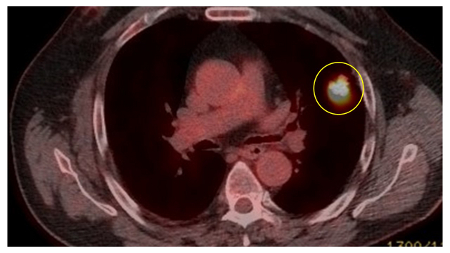

PET CT scan with 18-fluorodeoxyglucose (18-FDG) showing a high uptake peripheral left lung lesion. Surgical resection confirmed a moderately differentiated squamous cell lung cancer

From the collection of Dr George Tsaknis, MD, PhD, FRCP(London), MRQA, MAcadMEd, PGCert; used with permission